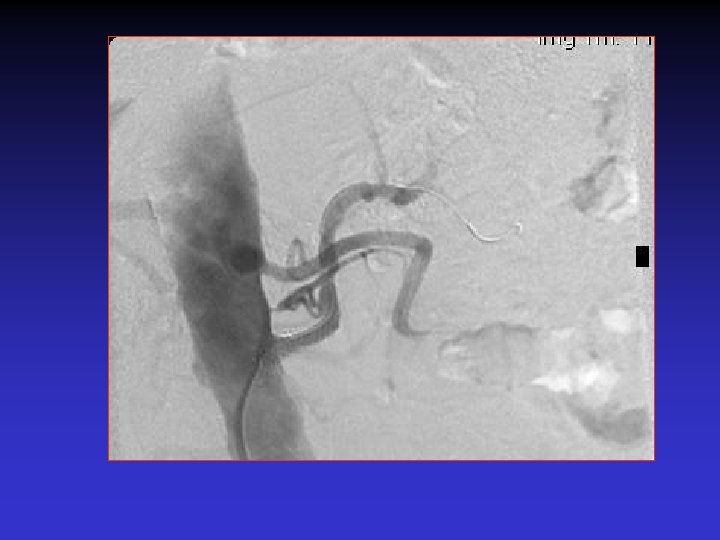

Is there any role for distal protection? • 65 hypertensive patients with significant RAS were stented with distal protection. • 2 protection devices were used: – Guardwire: 2 sizes [2. 5 -5 mm and 3 -6 mm] – Filterwire: 3. 5 -5. 5 mm] • Henry et al. Cath and cardio interv 2003

Results • ASA and plavix for 4 weeks. • Follow up: average 22 months; DSA if restenosis suspected by US. • Cr improved or stabilized in ALL patients. • The patients with moderate to severe renal impairment benefited the most. • Blood pressure control in all.

Distal protection devices • Visible debris in filter in all cases. • Atheromatous plaques, necrotic cores, thrombi, macrophages.